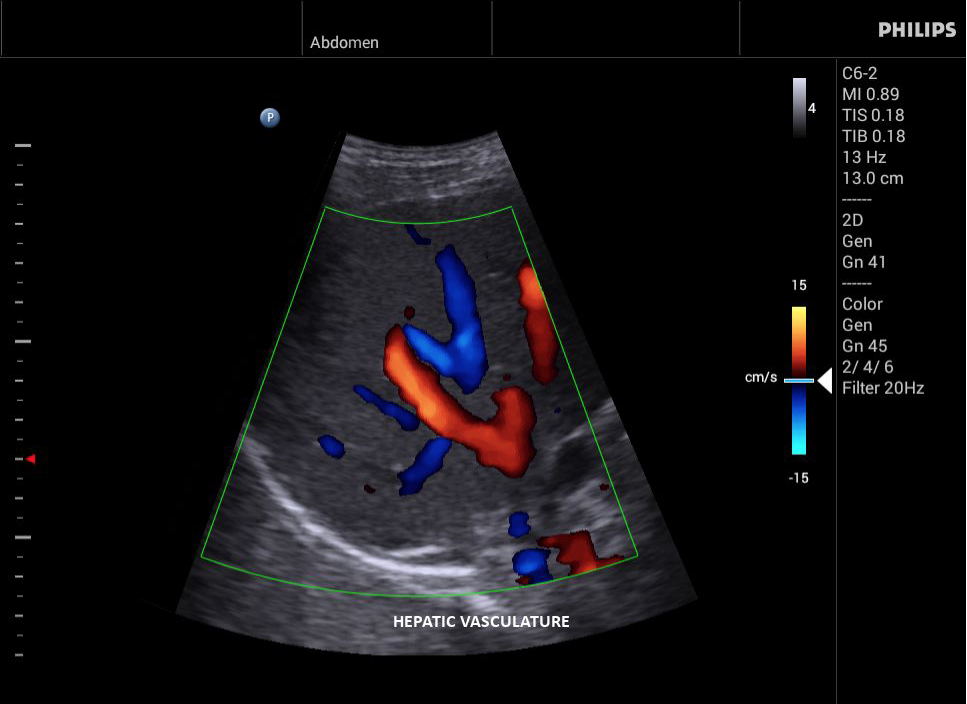

• Исследования сосудов;

• Цветное допплеровское картирование

• Направленный энергетический допплеровский режим: Дополнительно к возможностям визуализации сосудов в стандартном энергетическом режиме добавляется информация о направлении. Этот режим полезен для визуализации мелких сосудов в качестве замены цветного допплеровского картирования.

• Конвексный УЗИ датчик Philips С6-2